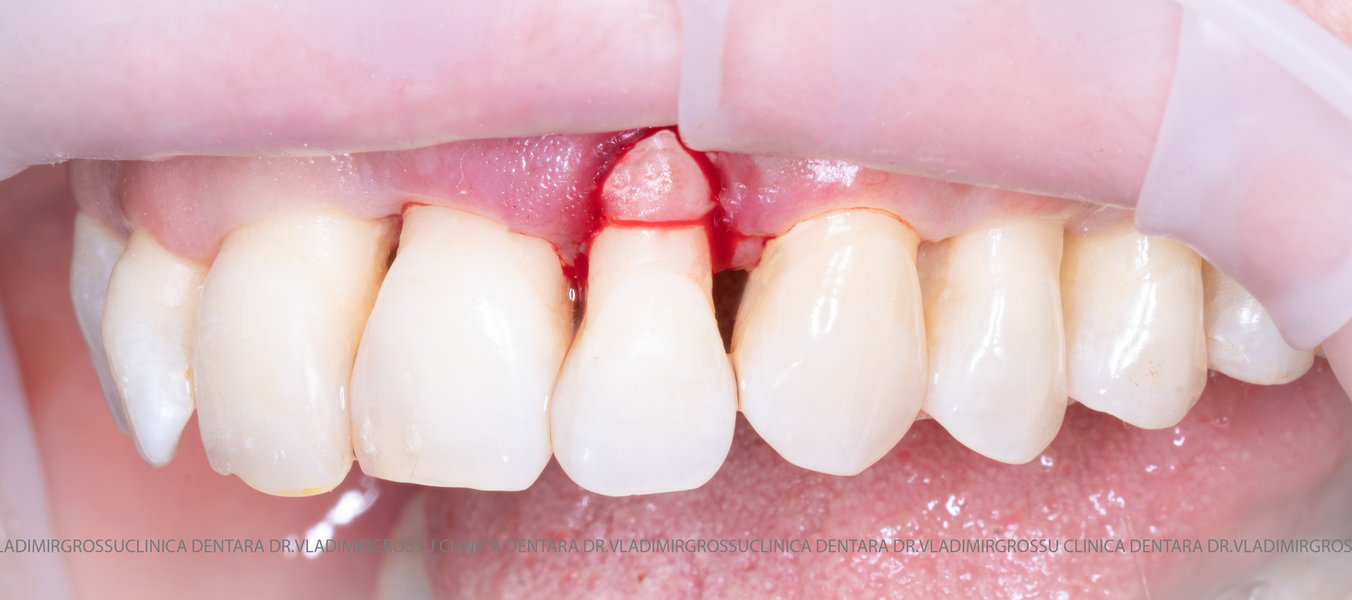

Aditia gingivală este o procedură chirurgicală ce corectează diverse probleme estetice și funcționale, cum ar fi recesiunea gingivală. În implantologia modernă, aditia de țesut moale este utilizată aproape în fiecare intervenție de inserție a implantului dentar pentru a asigura un aspect estetic natural și o bună integrare a implantului în cavitatea bucală.